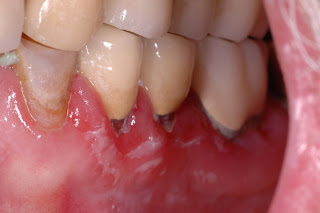

| Erosive Oral Lichen Planus |

A: Oral lichen planus is a chronic disease that can be controlled but not eliminated. A goal of therapy is to convert bothersome erosive lichen planus to the asymptomatic lacy (reticular) form. This requires some maintenance to keep the disease under control. Since oral lichen planus is incurable, flare-ups requiring additional therapy can occur.